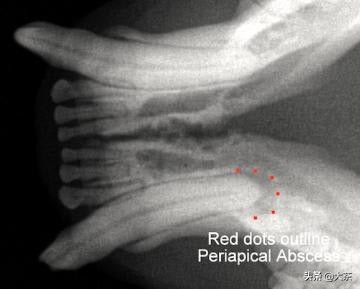

断牙之后,口腔里的细菌进入牙髓并感染牙齿,具有生命力的牙齿最终会死亡并成为细菌的天堂。由于牙髓死亡,这个时候猫咪不再感觉疼痛,但是细菌会沿着牙齿深入,直到感染牙槽骨。骨骼感染会再次带来剧烈疼痛,甚至引发猫咪面部脓肿以及全身感染。

这只猫咪断牙一年多,可以看到红点区域的牙根和骨骼已经被细菌感染破坏